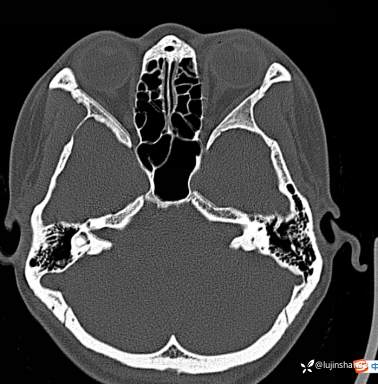

第一次术前颞骨CT及MRI: